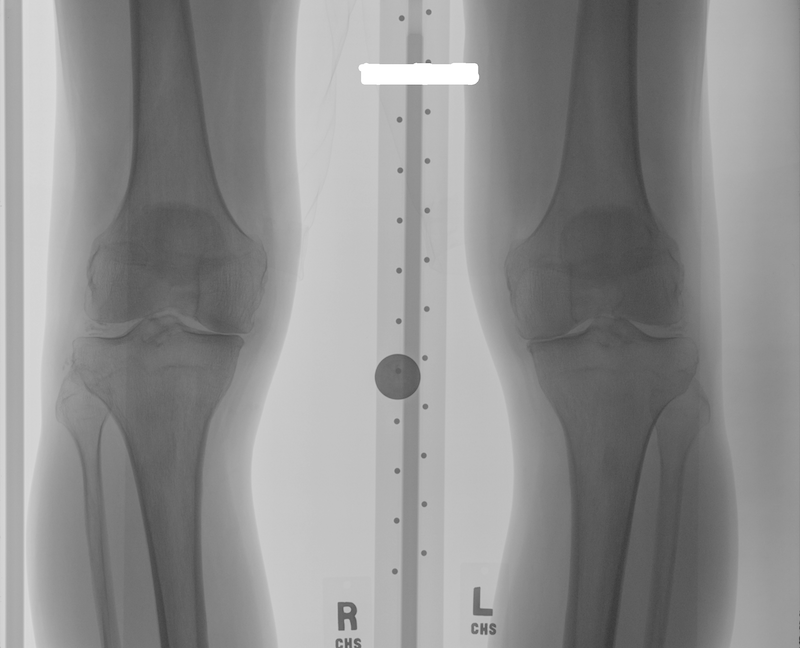

The data used for the experiments and analysis in this study are bilateral PA fixed flexion knee X-ray images. Figure 3 shows some samples of knee X-ray images from the dataset. Due to variations in X-ray imaging protocols, there are some visible artefacts in the X-ray images (Figure 3).

Refer to caption

Figure 3: Samples of bilateral PA fixed flexion knee OA radiographs.

The datasets are from the Osteoarthritis Initiative (OAI) and Multicenter Osteoarthritis Study (MOST) in the University of California, San Francisco. These are standard public datasets used in knee osteoarthritis studies.

Classification of knee OA images and the assessment of severity conditions can be achieved by examining the characteristic features of knee OA: variations in the joint space width and the osteophytes (bone spurs) formations in the knee joints [6]. Radiologists and medical practitioners examine only the knee joint regions in the X-ray images to assess knee OA. Hence, the region of interest (ROI) for classifying knee OA images is only the knee joint regions (left and right knees). Figure 6 shows the ROI in a X-ray image. The author believes that it is better to focus on the ROI instead of the entire X-ray image for accurate classification and this is also computationally economical. For these reasons, automatically detecting and extracting the knee joint regions from the X-ray images becomes an essential pre-processing step, before classification.

Figure 6: A knee OA X-ray image with the region of interest: the knee joints.